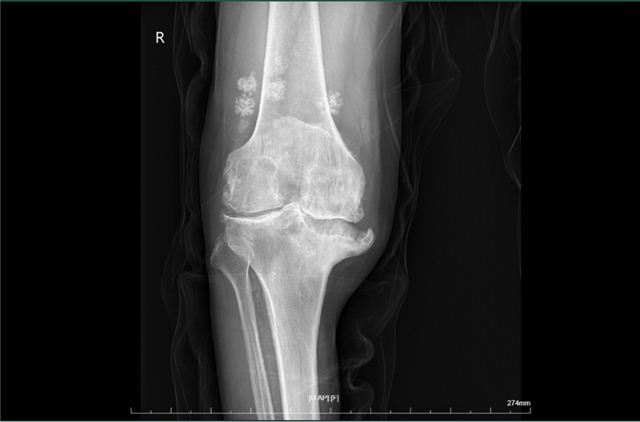

经过检查,结果提示该患者双膝重度骨关节炎,内翻畸形,内翻约20度,内侧平台塌陷约2cm。诊断很明确,双膝骨性关节炎。

术前X片